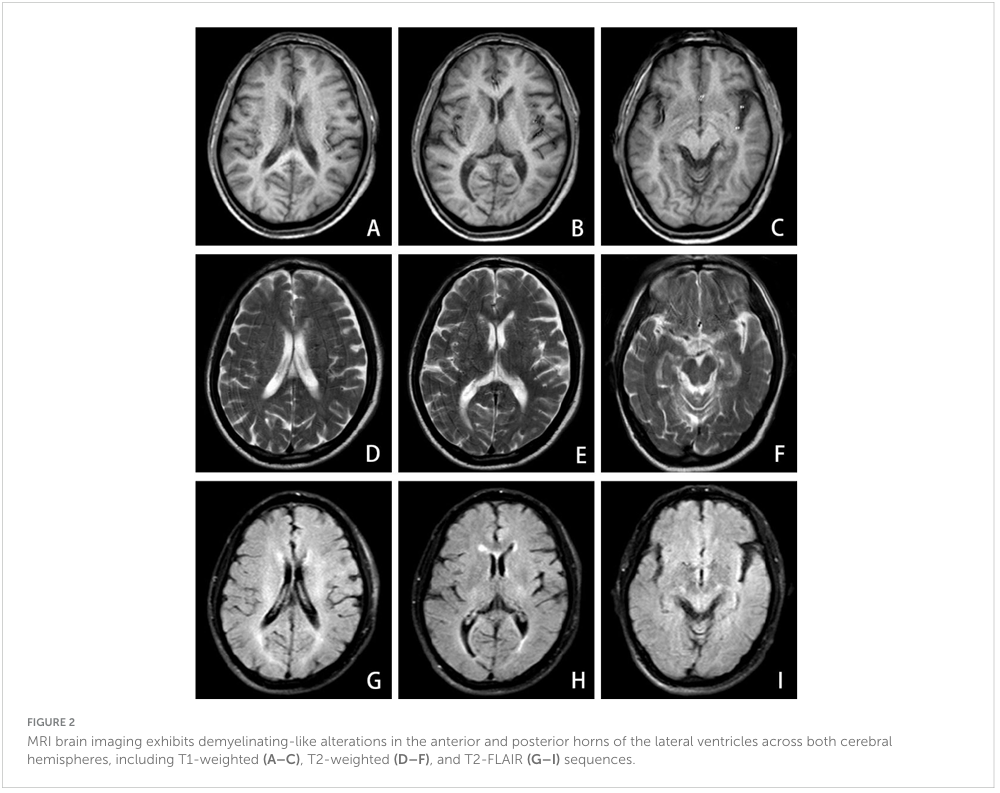

뇌 MRI에서는 위축 소견과 전두두정엽에 산재한 경미한 허혈 병변이 관찰되었으나, 뇌 CT는 정상이었다(Figure 2).